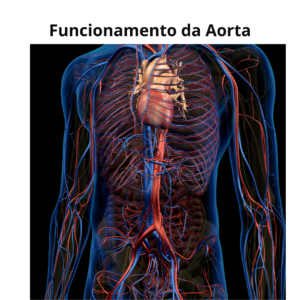

Aneurisma de Aorta e Dissecção de Aorta: O que é e como tratar? 1 – O que é a Aorta? A aorta é a maior

– Doenças do coração e aorta